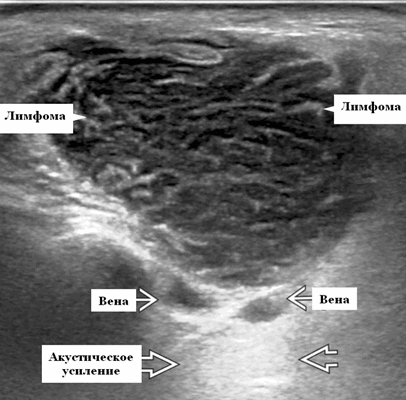

- Узловая неходжкинская лимфома (НХЛ): одиночные или множественные увеличенные яйцевидные внутрипаротидные лимфатические узлы, которые на УЗИ гомогенно гипоэхогенны по отношению к паренхиме околоушной железы, эхо-картина сетчатая. Заднее акустическое усиление. Выраженная внутриузловая гиперваскуляризация

Серошкальное УЗИ. Узловая НХЛ. Одиночные или множественные увеличенные яйцевидные внутрипаротидные лимфатические узлы. Гомогенно гипоэхогенный по отношению к паренхиме околоушной железы. Сетчатый эхосигнал. Заднее акустическое усиление. Первичная паренхиматозная НХЛ. Рассеянный, неоднородный эхосигнал; нечеткие, гипоэхогенные, похожие на опухоль участки. В пунктате внутрикистозная или паренхиматозная кальцификация из-за конечной стадии воспалительного изменения. Небольшие кистозные области образуются из-за сдавления терминальных протоков лимфоидной гипертрофией. Множественные небольшие гипоэхогенные участки (представляют собой лимфоидные агрегаты), разбросанные на фоне ткани слюнной железы. Изменения могут имитировать хронический сиалоаденит и диагноз часто ставится при биопсии. На УЗИ необходимо искать аналогичное поражение других слюнных и слезных желез, фон синдром Шегрена, BLEL. Может иметь или не иметь перипаротидную и шейную лимфаденопатию